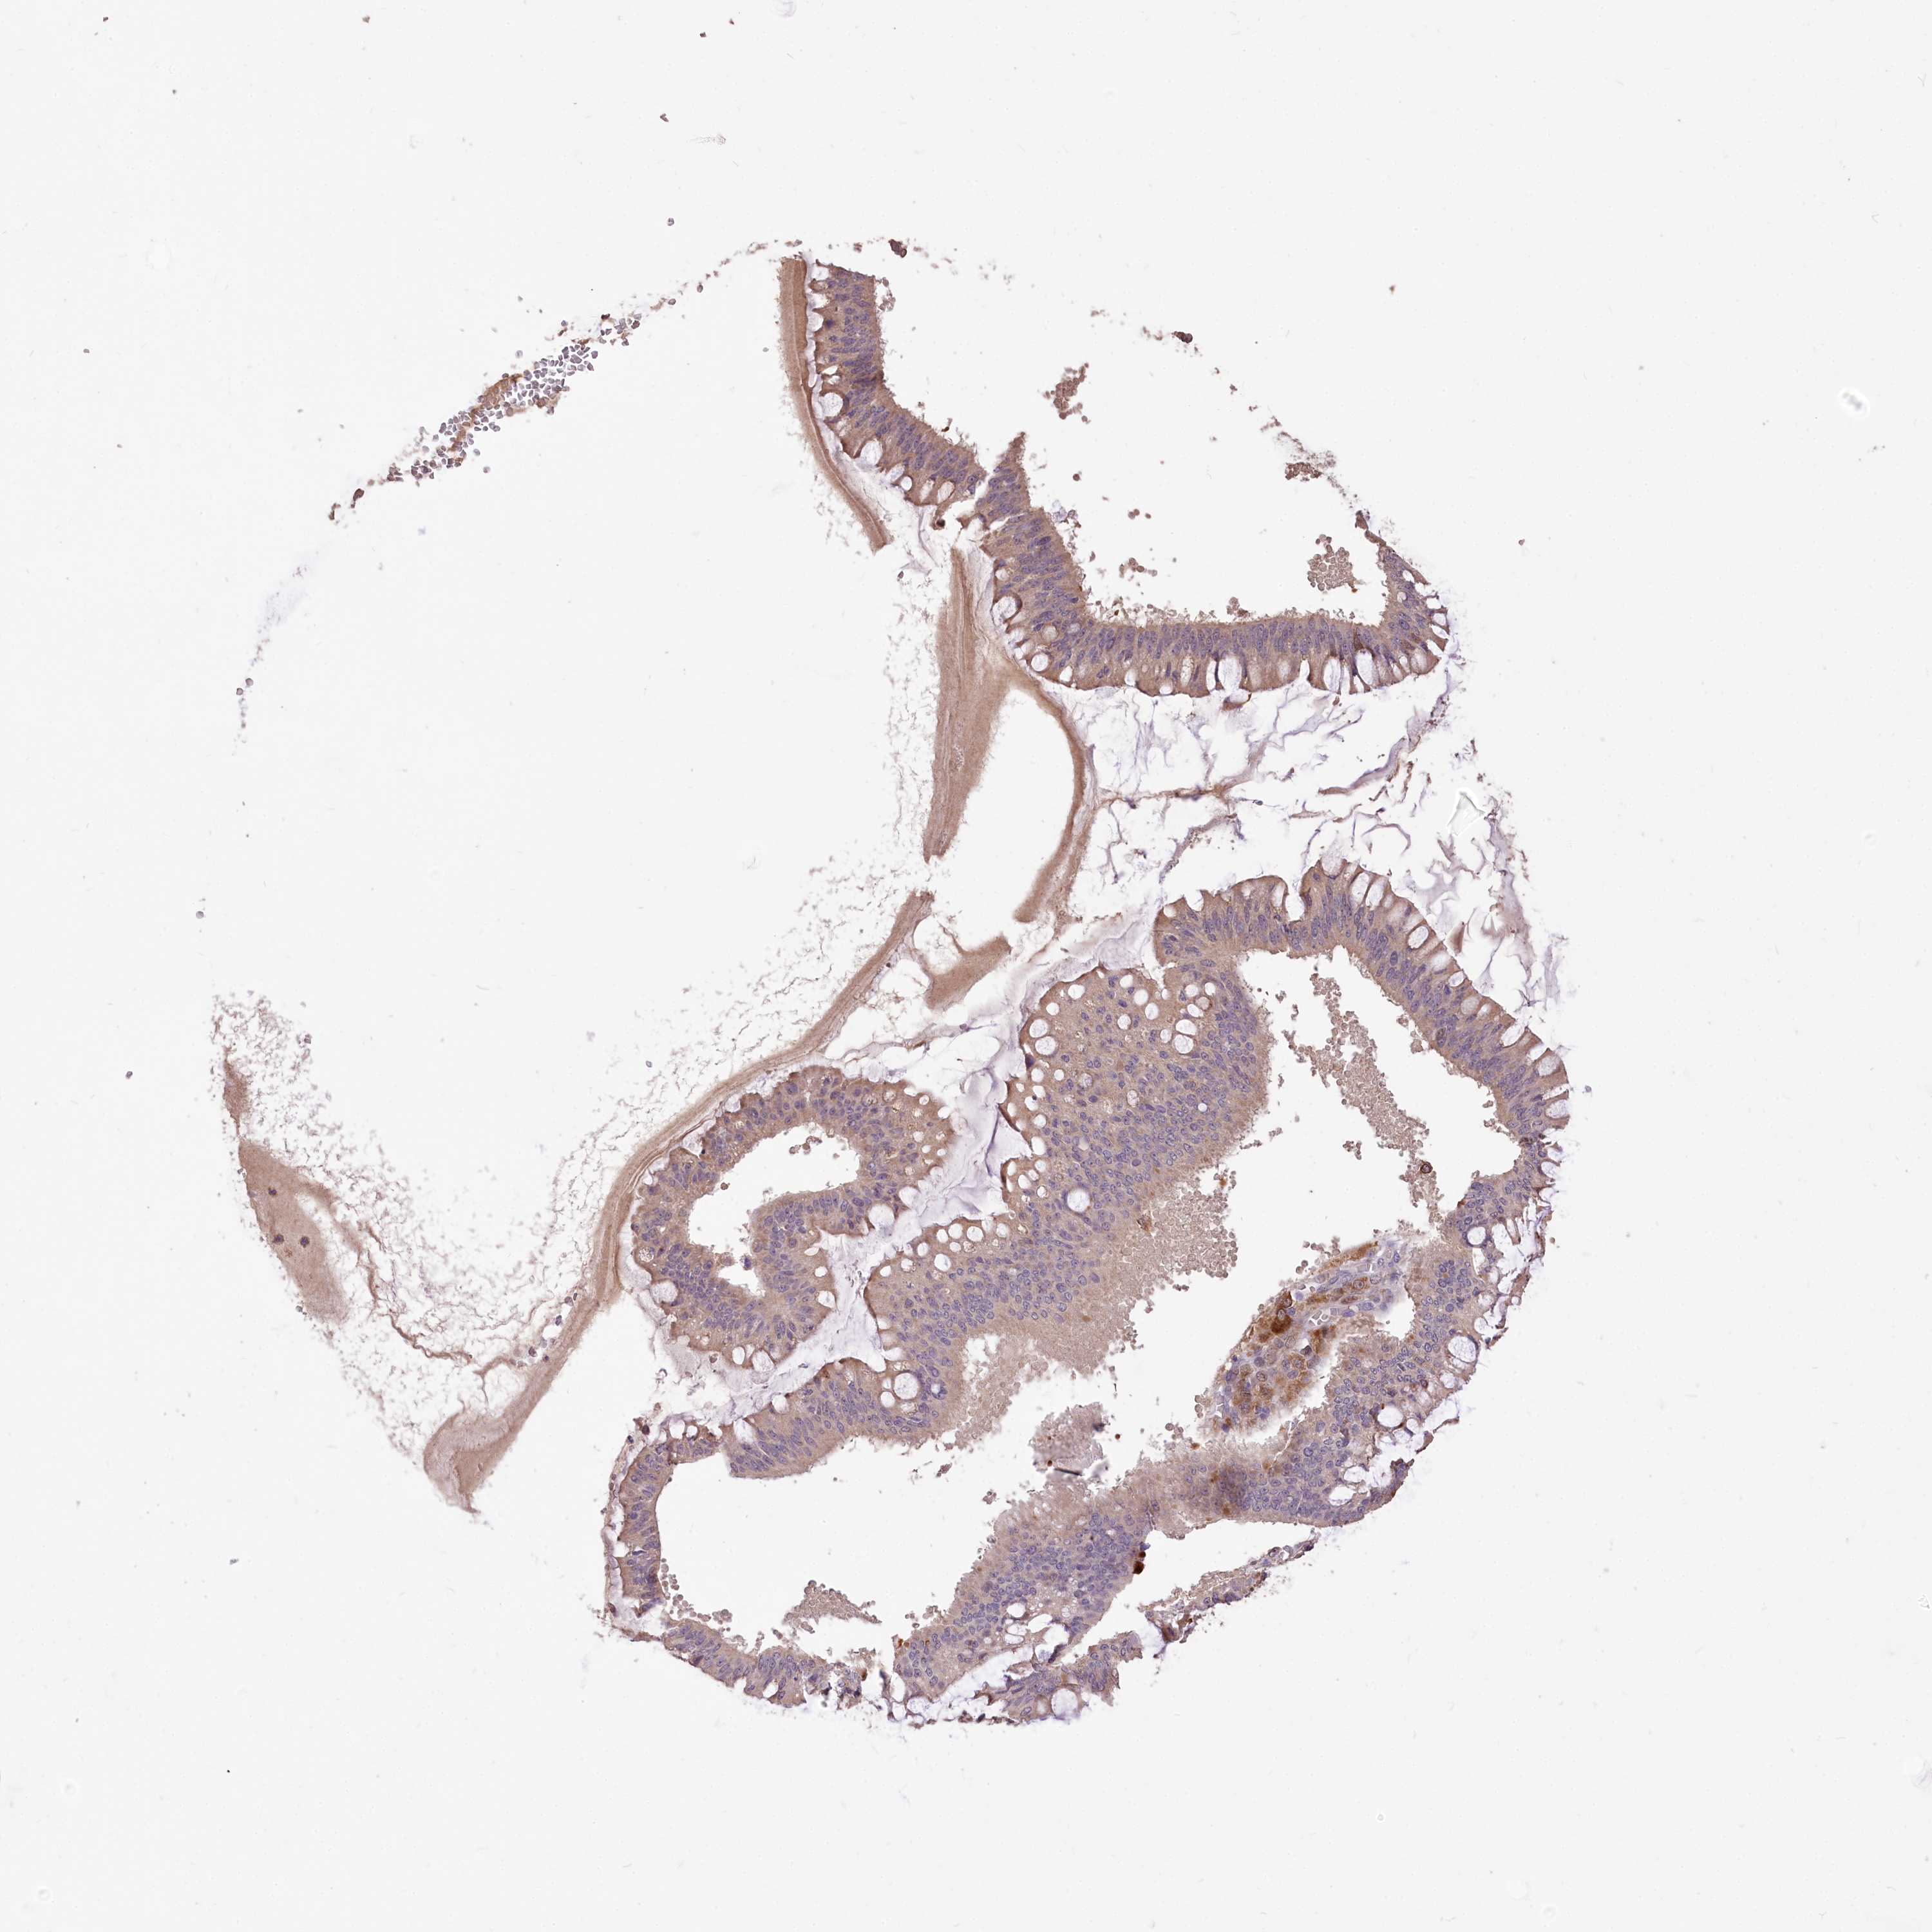

OVARIAN CANCER - Protein expressioni

A mouse-over function shows sample information and annotation data. Click on an image to view it in a full screen mode. Samples can be filtered based on level of antibody staining by selecting one or several of the following categories: high, medium, low and not detected. The assay and annotation is described here.

Note that samples used for immunohistochemistry by the Human Protein Atlas do not correspond to samples in the TCGA dataset.

Antibody stainingi

Antibody staining in the annotated cell types in the current human tissue is reported as not detected, low, medium, or high, based on conventional immunohistochemistry profiling in selected tissues. This score is based on the combination of the staining intensity and fraction of stained cells.

Each image is clickable and will lead to virtual microscopy that enables deeper exploration of all samples and also displays staining intensity scores, fraction scores and subcellular localization as well as patient and tissue information for each sample.

Antibody HPA037811

Antibody HPA037812

Cystadenocarcinoma, mucinous, NOS

Cystadenocarcinoma, serous, NOS